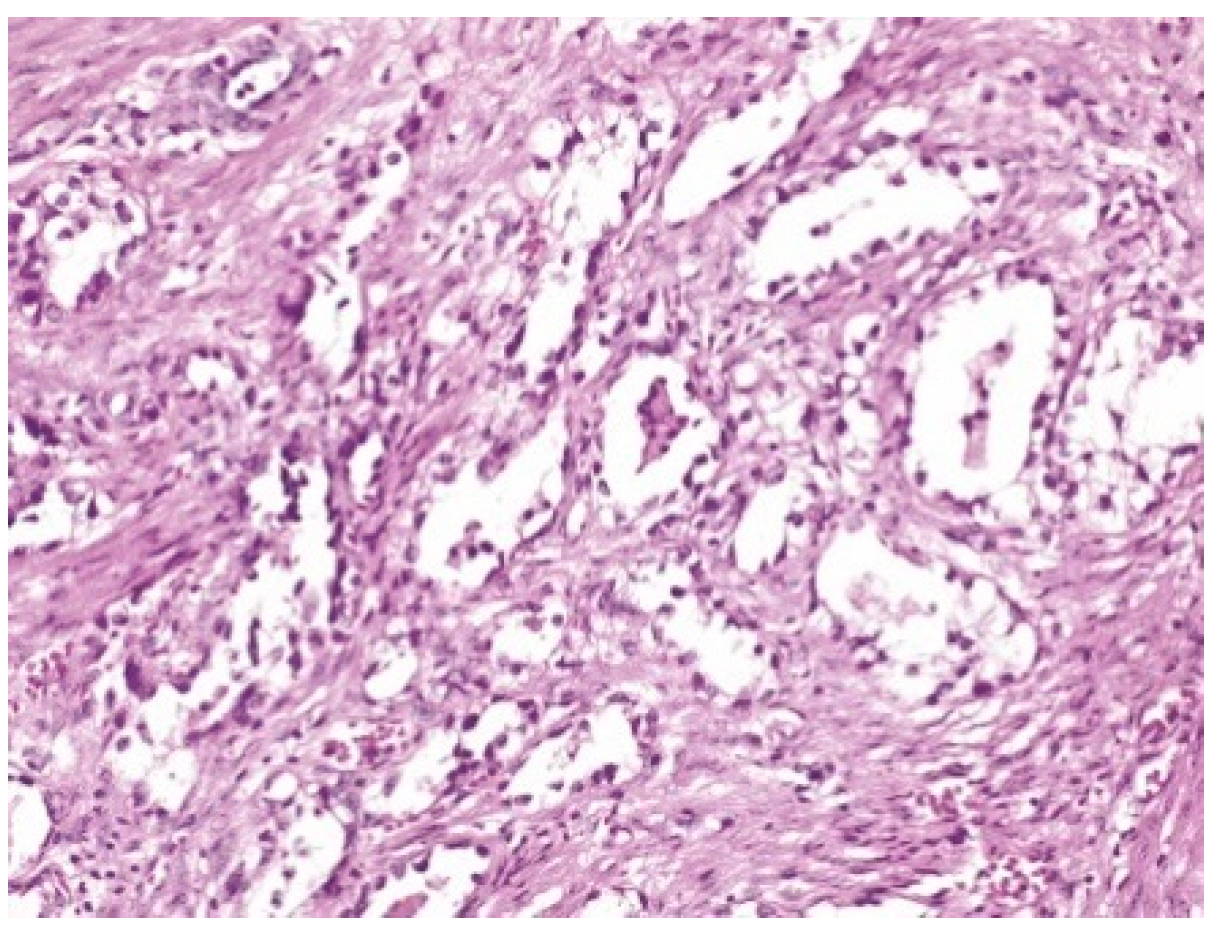

| LEEP | atypical mesonephric hyperplasia with a malignant transformation zone—mesonephric adeno-carcinoma with moderate cell pleomorphism, moderate mitotic activity, without invasion of the lymphovascular space, resection limits tangential to the lesion |

| Cervix with previous conization –appearance of atypical mesonephric hyperplasia; zone of stromal invasion and malignant transformation—endocervical mesonephric adenocarcinoma with moderate cell pleomorphism and mitotic activity, intraluminal detritus, added inflammation | |